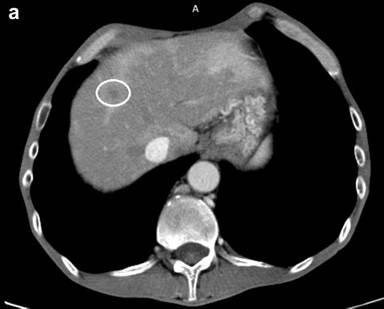

In January 2013 a new FOLFOX4 combination therapy was prescribed after a multidisciplinary team meeting (MDT) due to significant progression of the pathological process on control CT and poor general condition of the patient. The tumor volume had increased and 4 newly discovered hypodense lesions with different size were identified in the liver (Figure 2a).

Figure 2. a. The contrast enhanced CT revealed newly found liver metastases (marked) suggestive of disease progression. b. The contrast enhanced CT image before HIFU showed a hypodense lesion of a liver metastasis about 14 mm in diameter in the right lobe (segment seven). c. Twelve months after the combination treatment with HIFU and chemotherapy the liver metastases were significantly reduced on the contrast control CT. |